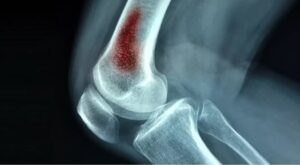

ایکس رے

ایکس رے ہڈی کو پہنچنے والا نقصان دکھاتے ہیں، تاہم یہ نقصان اس وقت تک ظاہر نہیں ہوتا جب تک اوسٹیو مائیلائٹس کئی ہفتوں سے موجود نہ ہو۔ اگر آپ کو حال ہی میں انفیکشن ہوا ہے تو مزید تفصیلی امیجنگ ٹیسٹ کی ضرورت ہو سکتی ہے۔